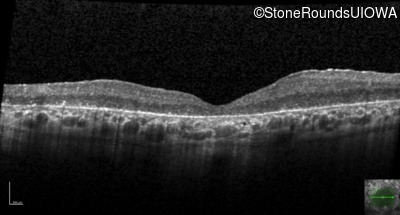

Exemplar / OCT Stack

OCT Stack